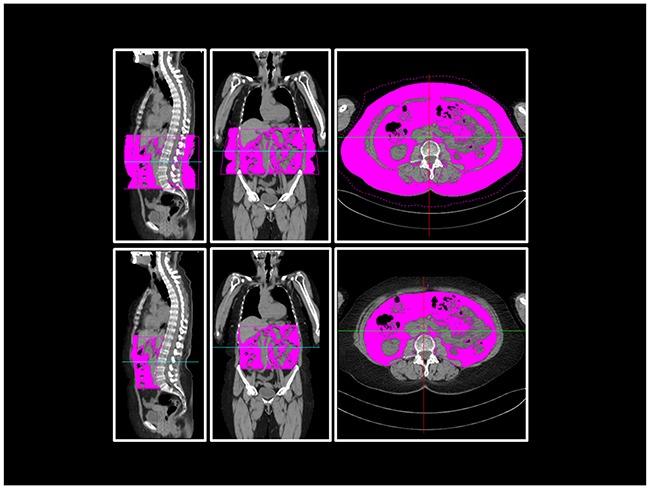

A subgroup of 108 patients from a single institution enrolled in the prospective GMMG-MM5 trial, who received a whole-body low-dose computed tomography (WBLDCT) before induction therapy, were included in this study. Body fat composition was measured in WBLDCT for each patient, divided in the compartments abdomen, pelvis, thigh and further categorized in subcutaneous (SAT) and visceral adipose tissue (VAT). The correlation of these parameters with disease activity (M protein, plasma cell count, LDH, CRAB-criteria), adverse cytogenetics, adverse events and treatment response were evaluated.

本研究纳入了来自单个机构的108例患者,这些患者参与了前瞻性GMMG-MM5试验,在诱导治疗前接受了全身低剂量计算机断层扫描(WBLDCT)。通过WBLDCT测量每位患者的体脂成分,分为腹部、骨盆、大腿等部位,并进一步分为皮下脂肪(SAT)和内脏脂肪组织(VAT)。评估这些参数与疾病活动(M蛋白、浆细胞计数、乳酸脱氢酶、CRAB标准)、不良细胞遗传学、不良事件及治疗反应之间的相关性。